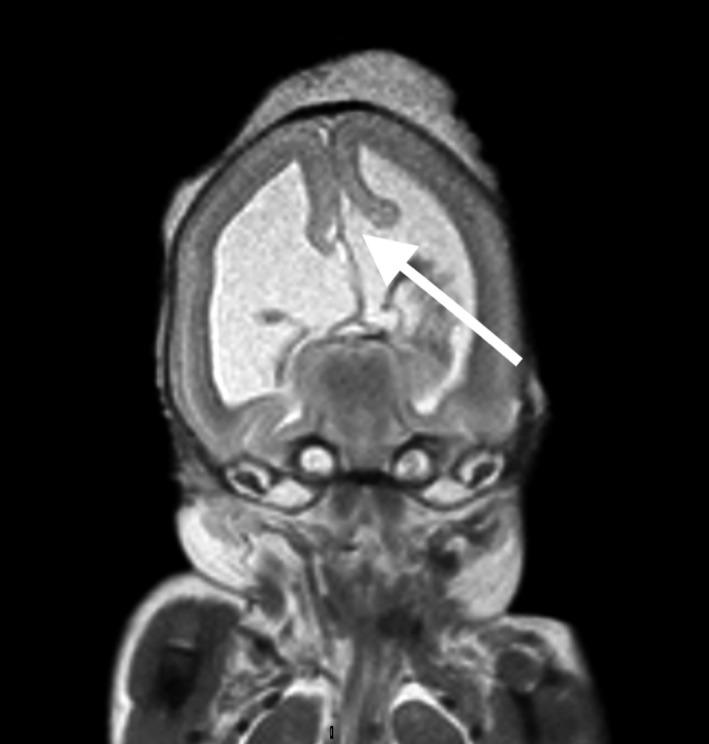

中孕期因畸形而终止妊娠胎儿的死后磁共振成像与尸检比较

Postmortem magnetic resonance imaging vs autopsy of second trimester fetuses terminated due to anomalies.

Our aim was to investigate the accuracy of postmortem fetal magnetic resonance imaging (MRI) compared with fetal autopsy in second trimester pregnancies terminated due to fetal anomalies. A secondary aim was to compare the MRI evaluations of two senior radiologists.

MATERIAL AND METHODS

This was a prospective study including 34 fetuses from pregnancies terminated in the second trimester due to fetal anomalies. All women accepted a postmortem MRI and an autopsy of the fetus. Two senior radiologists performed independent evaluations of the MRI images. A senior pathologist performed the fetal autopsies. The degree of concordance between the MRI evaluations and the autopsy reports was estimated as well as the consensus between the radiologists.

RESULTS

Thirty-four fetuses were evaluated. Sixteen cases were associated with the central nervous system (CNS), five were musculoskeletal, one cardiovascular, one was associated with the urinary tract, and 11 cases had miscellaneous anomalies such as chromosomal aberrations, infections and syndromes. In the 16 cases related to the CNS, both radiologists reported all or some, including the most clinically significant anomalies in 15 (94%; CI 70%-100%) cases. In the 18 non-CNS cases, both radiologists reported all or some, including the most clinically significant anomalies in six (33%; CI 5%-85%) cases. In 21 cases (62%; CI 44%-78%), both radiologists held opinions that were consistent with the autopsy reports. The degree of agreement between the radiologists was high, with a Cohen's Kappa of 0.87.

CONCLUSIONS

Postmortem fetal MRI can replace autopsy for second trimester fetuses with CNS anomalies. For non-CNS anomalies, the concordance is lower but postmortem MRI can still be of value when autopsy is not an option.

我们的目的是研究与因胎儿畸形而终止妊娠的胎儿中孕期尸检相比,胎儿磁共振成像(MRI)的准确性。次要目的是比较两位资深放射科医生的 MRI 评估结果。

材料与方法

这是一项前瞻性研究,纳入了 34 例因胎儿畸形而在中孕期终止妊娠的胎儿。所有女性均接受了胎儿死后 MRI 和胎儿尸检。两位资深放射科医生对 MRI 图像进行了独立评估。一位资深病理学家进行了胎儿尸检。MRI 评估与尸检报告的一致性程度以及放射科医生之间的共识程度均进行了评估。

结果

共评估了 34 例胎儿。16 例与中枢神经系统(CNS)有关,5 例与肌肉骨骼系统有关,1 例与心血管系统有关,1 例与泌尿系统有关,11 例有多种异常,如染色体异常、感染和综合征。在与 CNS 相关的 16 例病例中,两位放射科医生均报告了所有或部分病例,包括 15 例(94%;CI 70%-100%)最具临床意义的异常。在 18 例非 CNS 病例中,两位放射科医生均报告了所有或部分病例,包括 6 例(33%;CI 5%-85%)最具临床意义的异常。在 21 例(62%;CI 44%-78%)病例中,两位放射科医生的意见与尸检报告一致。两位放射科医生的意见一致性较高,Cohen's Kappa 值为 0.87。

结论

对于中枢神经系统畸形的中孕期胎儿,死后胎儿 MRI 可替代尸检。对于非 CNS 异常,一致性较低,但当无法进行尸检时,死后 MRI 仍然具有价值。